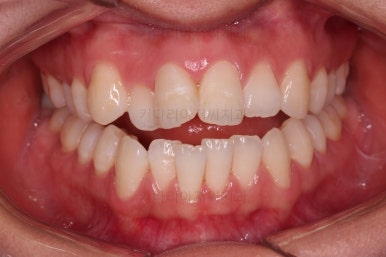

부산교정잘하는치과 전후 비교해 보겠습니다.

치열도 당연히 좋아졌지만 웃을 때 보이는 치열도 매우 예뻐졌습니다.

입매도 본인이 원하는 수준으로 딱 멈춰드렸고, 적절하게 자연스럽게 약간 들어가고 마무리가 되었습니다.

전반적으로 매우 만족하신 치료가 되었습니다.